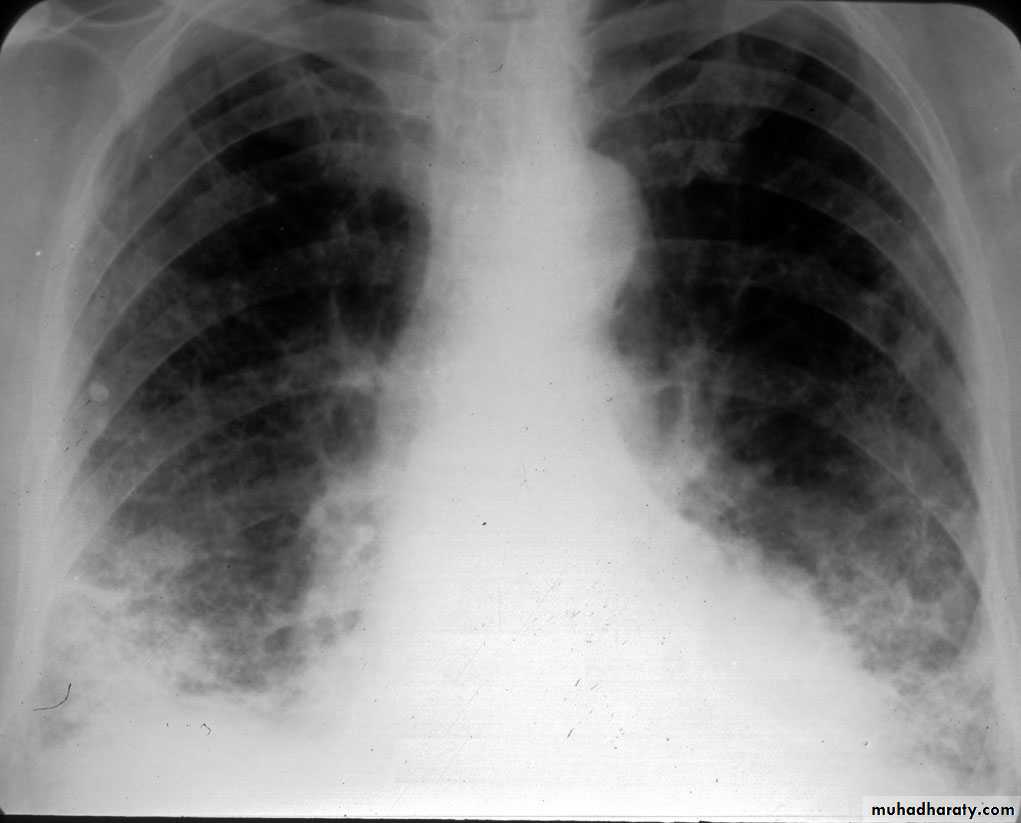

Chest X-ray: typically small lung volumes with reticulonodular shadowing

Abnormal chest X-ray at presentation with lower zone bi-basal reticular and reticulonodular opacities. 'honeycomb' appearance in advanced disease.

HRCT may be diagnostic, demonstrating a patchy, predominantly peripheral, subpleural and basal reticular pattern with subpleural cysts (honeycombing).